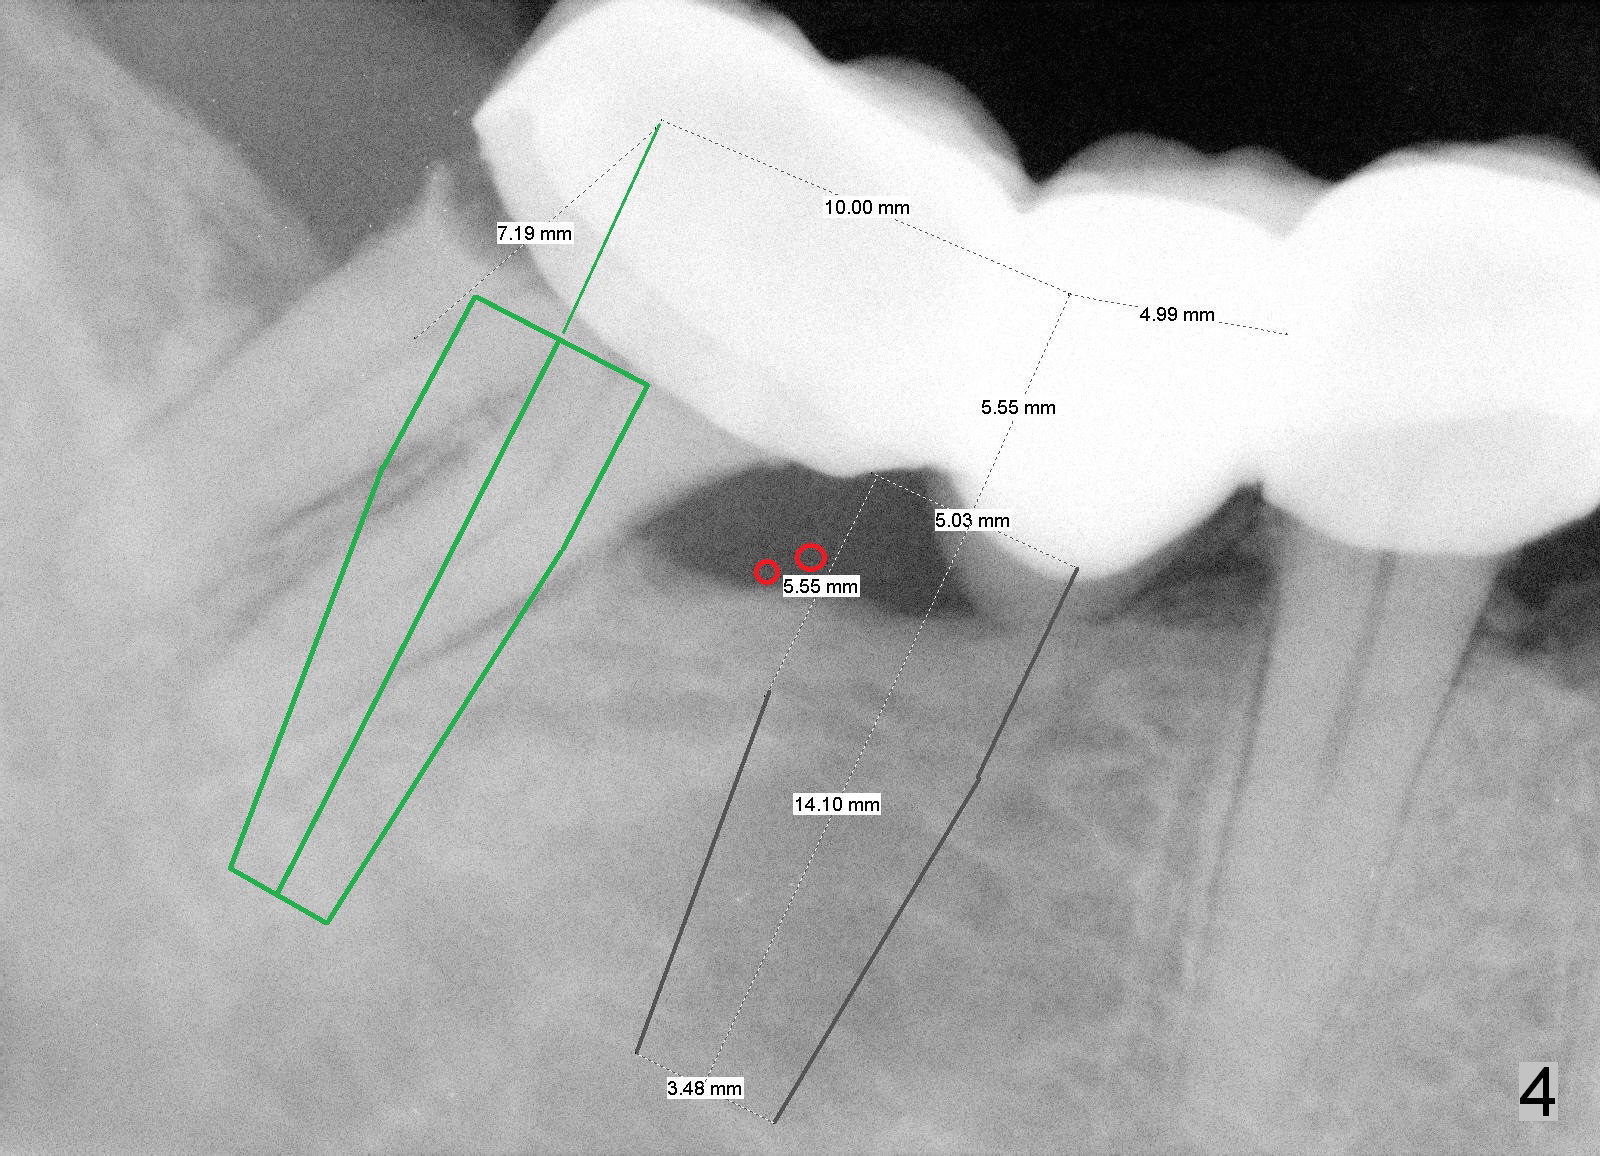

The length of tissue-level implants should be confined to 14 mm (Fig.4).

To ensure the position and trajectory of these 2 implants, impression will be taken prior to surgery for wax up and surgical stent fabrication.